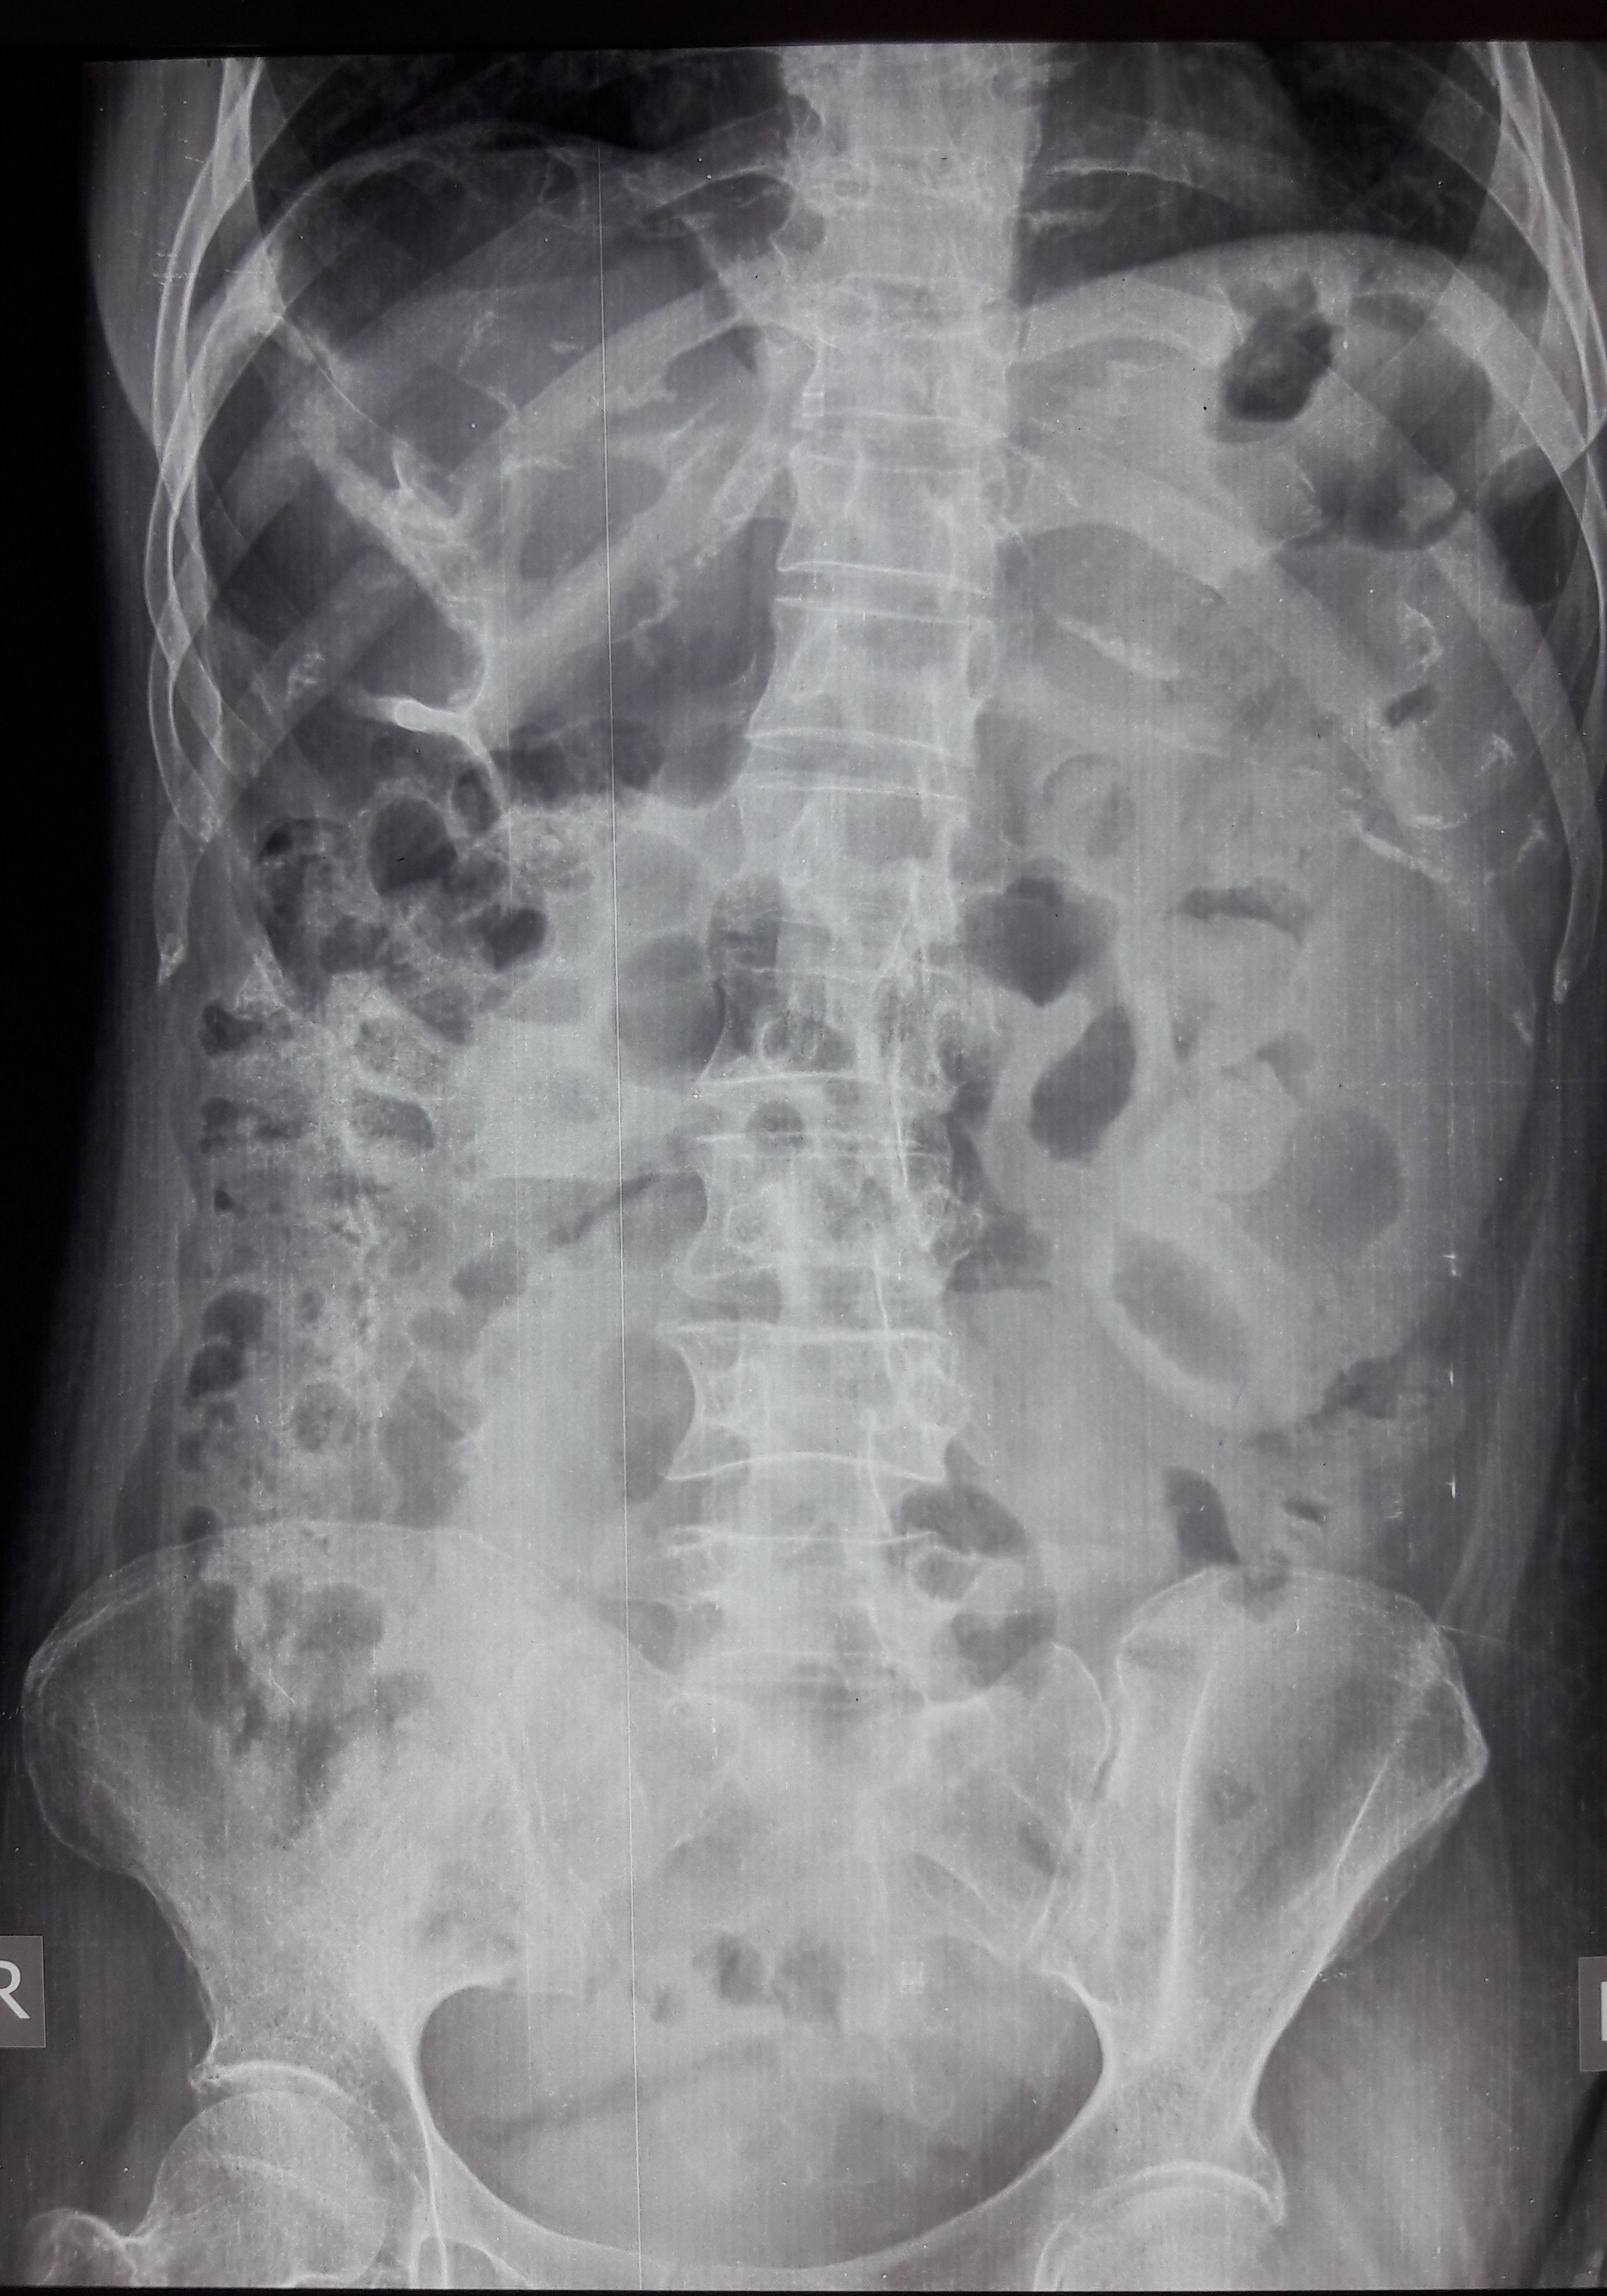

Ogilvie’s syndrome or acute colonic pseudo-obstruction is a rare and acquired disorder characterized by significant dilatation of the colon. The condition is mainly seen in hospitalized patients with medical or surgical problems. We report the case of a middle aged healthy lady who presented with Ogilvie’s syndrome with associated electrolyte imbalance in the form of hypokalemia and hypomagnesemia. Ogilvie’s syndrome itself is a rare condition, and to the best of our knowledge has not been reported among healthy individuals yet.